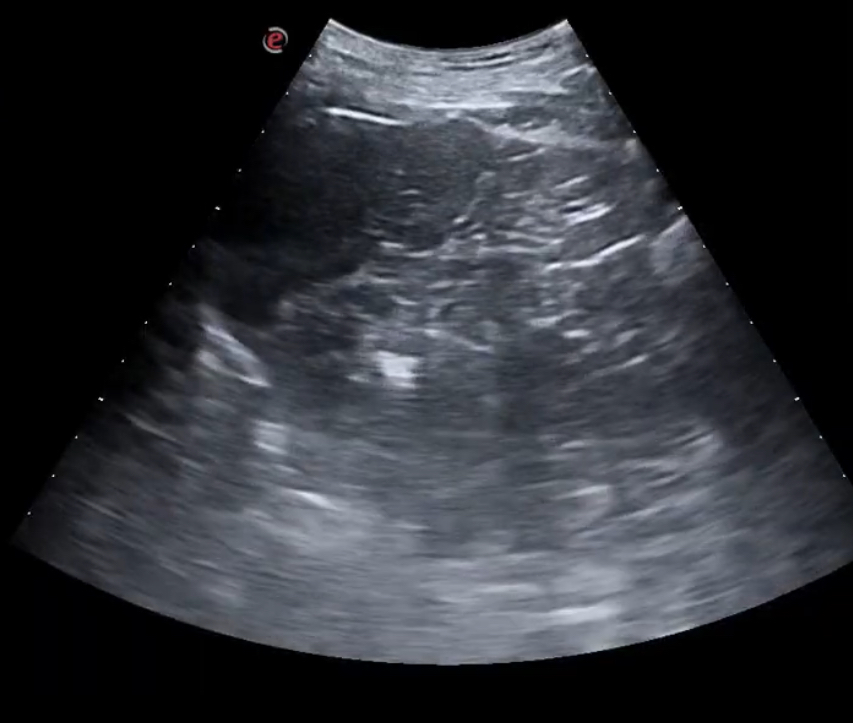

Se realiza ecografía clínica pulmonar observándose un patrón de consolidación en segmento 6 de pulmón derecho con líneas B acompañantes (mayor a 3).

Se revisó a los 15 días y el paciente presentaba una mejoría clínica, repitiéndose la ecografía y mostrando mejoría ecográfica sin presentar líneas B ni datos de condensación.

La ecografía clínica pulmonar es una herramienta muy sensible y específica que nos permite identificar lesiones que no llegan a ser visibles en la radiografía. La reproducibilidad de la técnica nos permite valorar la evolución del paciente en la propia consulta.